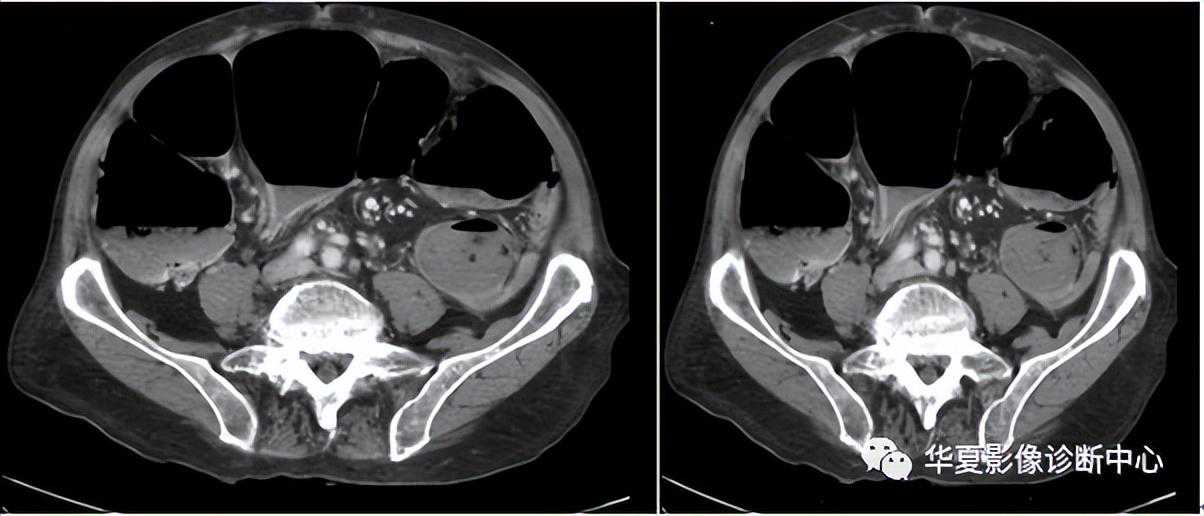

031:箭头征

阑尾炎CT的直接征象是阑尾形态的异常,表现为阑尾外径增粗和阑尾壁的增厚。正常阑尾的直径一般3~5mm,有些报道在阑尾腔内无对比剂的情况下,正常阑尾外径可达11mm。急性阑尾炎患者的阑尾平均直径达11mm。不能单凭阑尾增粗(>6mm)或阑尾壁增厚(>3mm)来诊断阑尾炎,必须结合其他征象综合考虑。

“箭头”征阑尾炎的一个比较典型的CT表现,是造影剂汇集在盲肠尖端(阑尾起始部)形成的箭头样、鸟嘴样改变,是阑尾炎症蔓延到盲肠尖肠壁的结果。如果在盲肠的尖端汇集的不是高密度的造影剂而是气体,那么显示的就是空箭头征。如果造影剂汇集于结肠憩室的口部,也会显示这样的征象。箭头征也见于急性阑尾炎的CT增强扫描中,急性阑尾炎患者的阑尾血流比率比正常肠道高,增强扫描时可见其强化。部分患者由于炎症时肠壁血管内血栓形成,使局部血流受阻,阑尾血流比率可等于或低于正常肠道,甚至无血流灌注,CT上阑尾表现为等密度,低强化或无强化;另外阑尾炎时,其邻近肠管可继发炎症,局部血流增加,有时CT上可见局部盲肠壁增粗,强化时增强,似箭头一样指向病变阑尾。“箭头”征是造影剂汇集在盲肠尖端(阑尾起始部)形成的箭头样、鸟嘴样改变,是阑尾炎症蔓延到盲肠肠壁的结果。见到此征象,有文献报道,阑尾炎的特异度几达100%。有些患者由于炎症较轻,肠道血流可无明显改变;也有些病例,可能是肠壁部分血流受阻,与炎症引起的血管扩张相抵消。因而其血运明显受阻,局部造影剂减少所致。